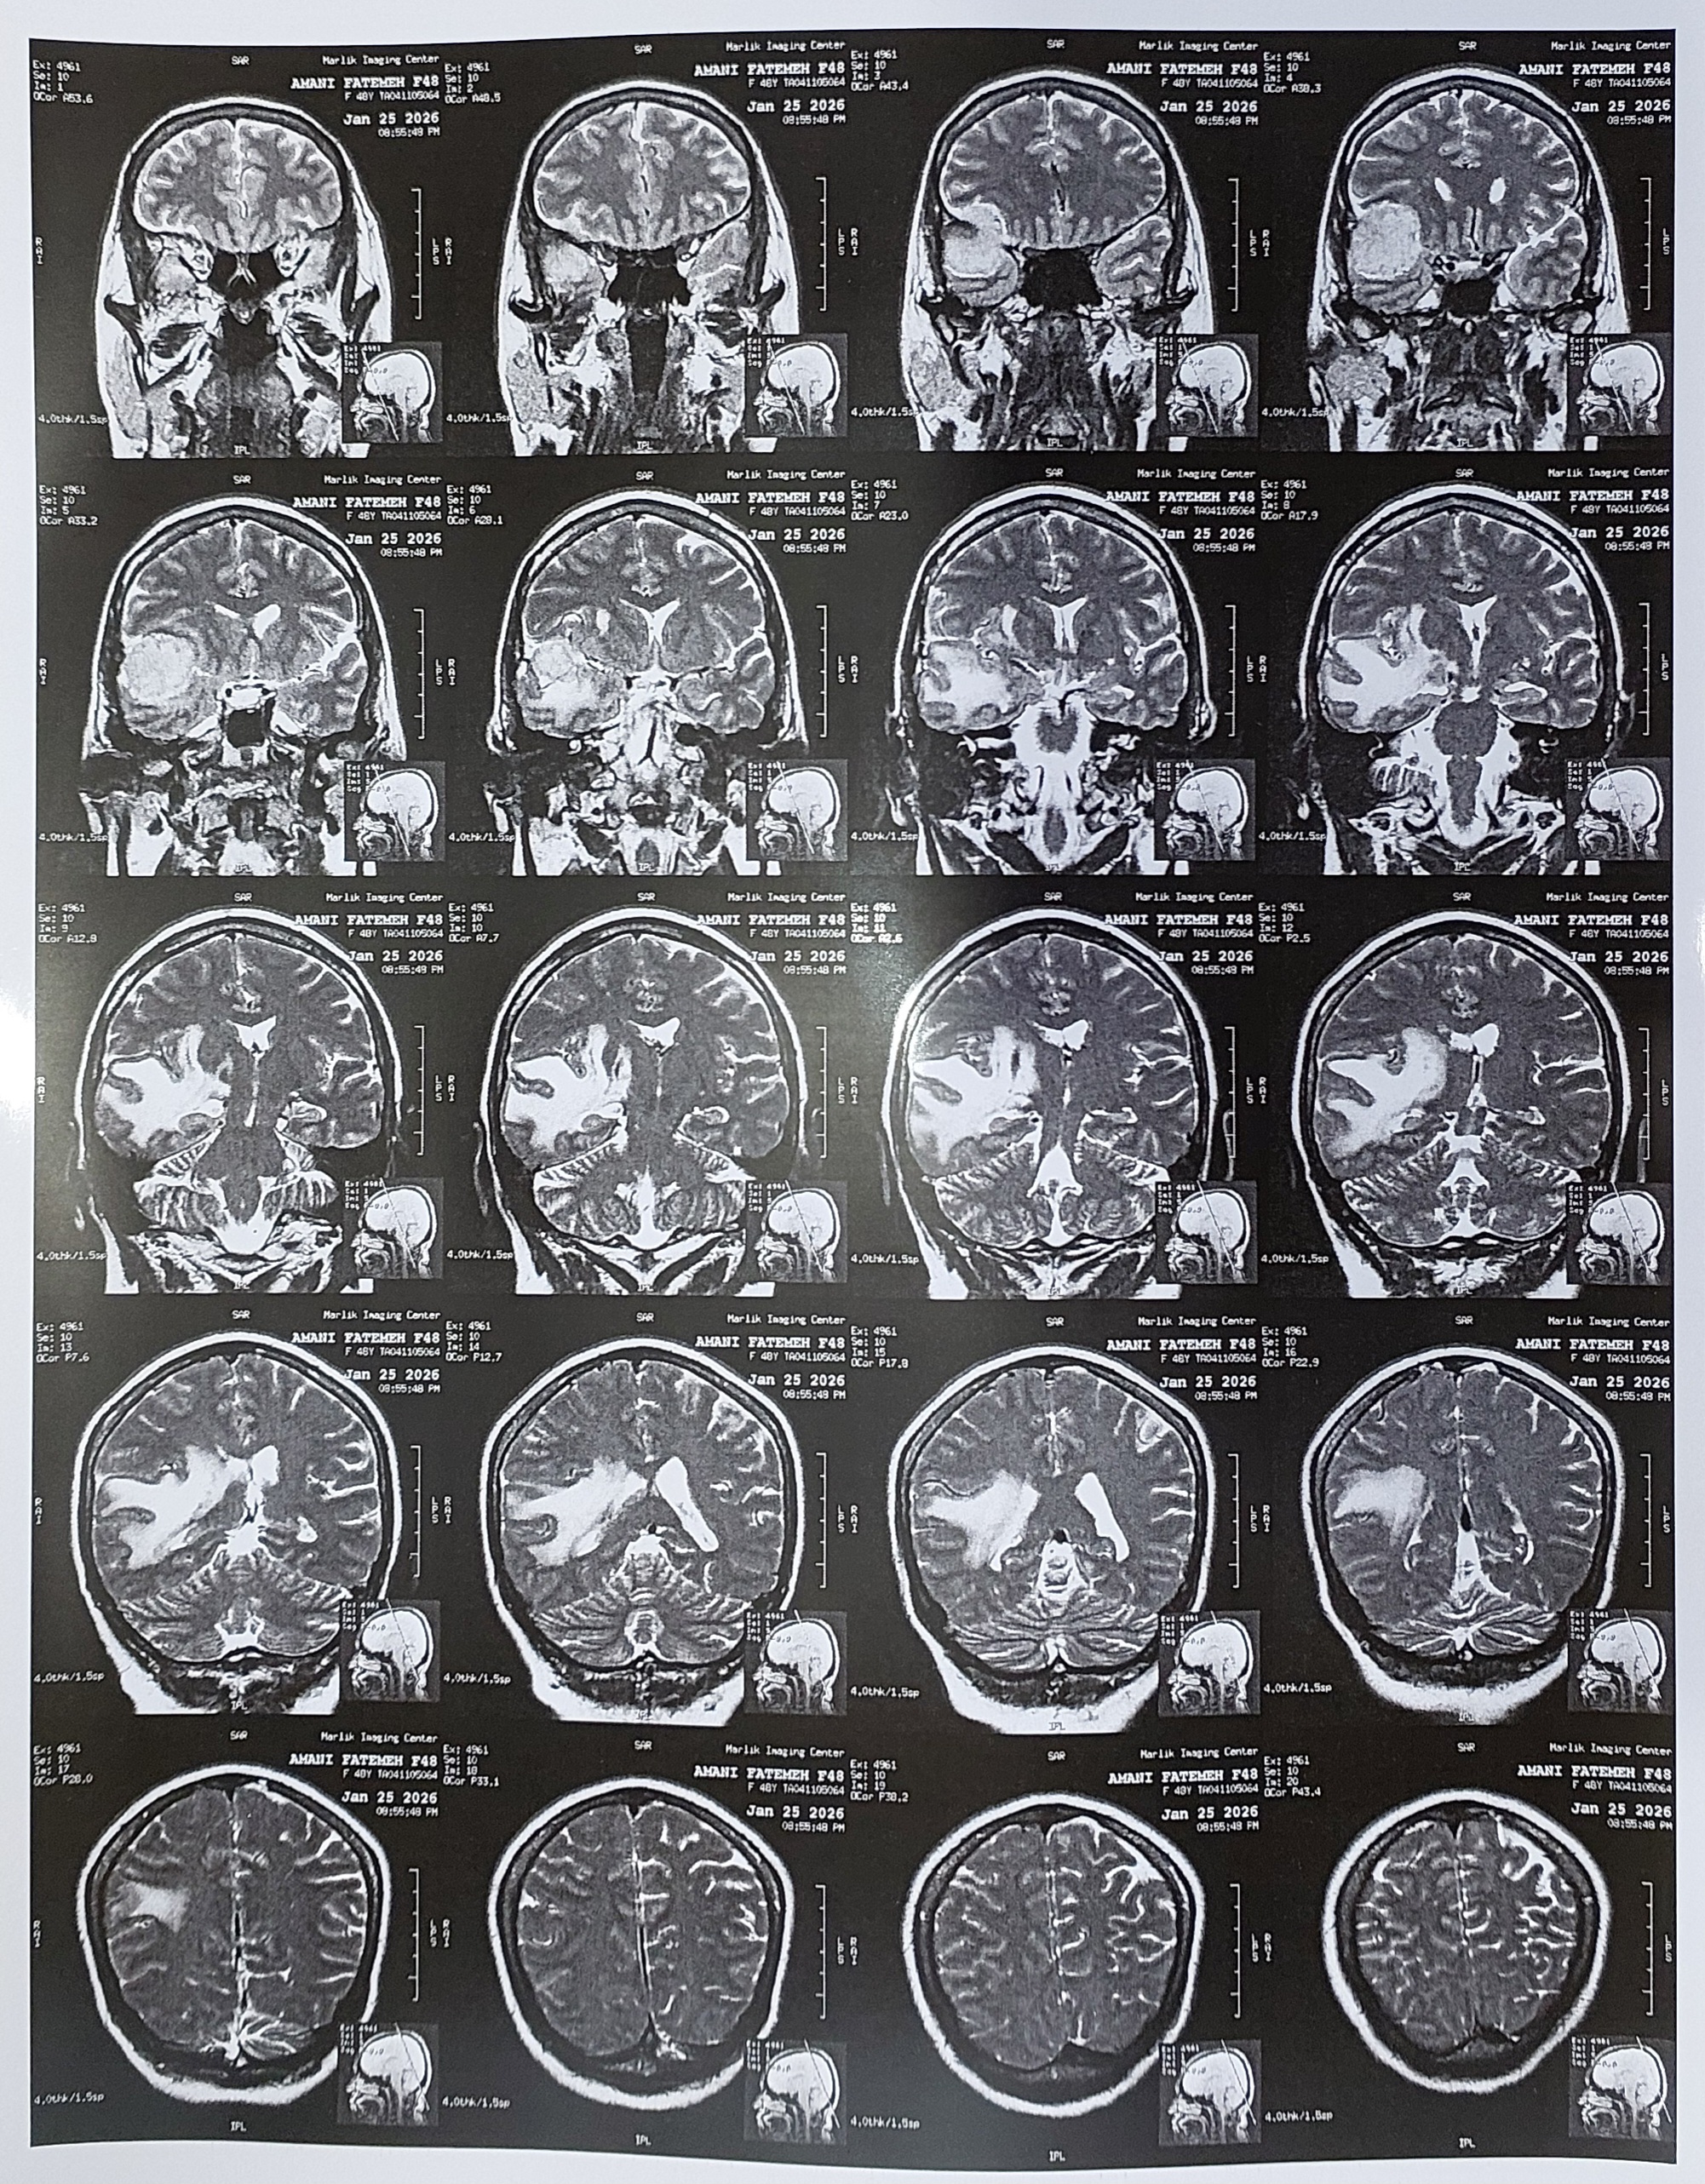

Brain MRI

On T1, T 2 weighted and FLAIR sequences with sagittal, axial and coronal sections:

There is a rather large tumoral mass about 37*32mm in the right temporal lobe

extended to deep portion of right frontal lobe with severe edema and mass effect

causing pressure effect upon right latera ventricle and mildly midline shift due to

such as GBM,..?!

brain trauma For more survey MRI with gadolinium injection is recommended.

The structure of mid brain and pons appear normal.

nerves complex ,

th & 8th The cerebellopontine (CP) angles , internal auditory canals , 7brain stem & cerebellum, vermis and medulla have normal appearance.